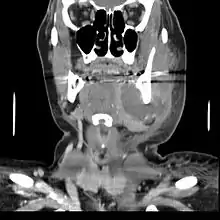

If left untreated, a severe tooth abscess may become large enough to perforate bone and extend into the soft tissue eventually becoming osteomyelitis and cellulitis respectively. From there it follows the path of least resistance and may spread either internally or externally. The path of the infection is influenced by such things as the location of the infected tooth and the thickness of the bone, muscle and fascia attachments.

Internal drainage is of more concern as growing infection makes space within the tissues surrounding the infection. Severe complications requiring immediate hospitalization include Ludwig's angina, which is a combination of growing infection and cellulitis which closes the airway space causing suffocation in extreme cases. Also infection can spread down the tissue spaces to the mediastinum which has significant consequences on the vital organs such as the heart. Another complication, usually from upper teeth, is a risk of sepsis traveling through pathways to which it can possibly lead to endocarditis, brain abscess (extremely rare), or meningitis (also rare).